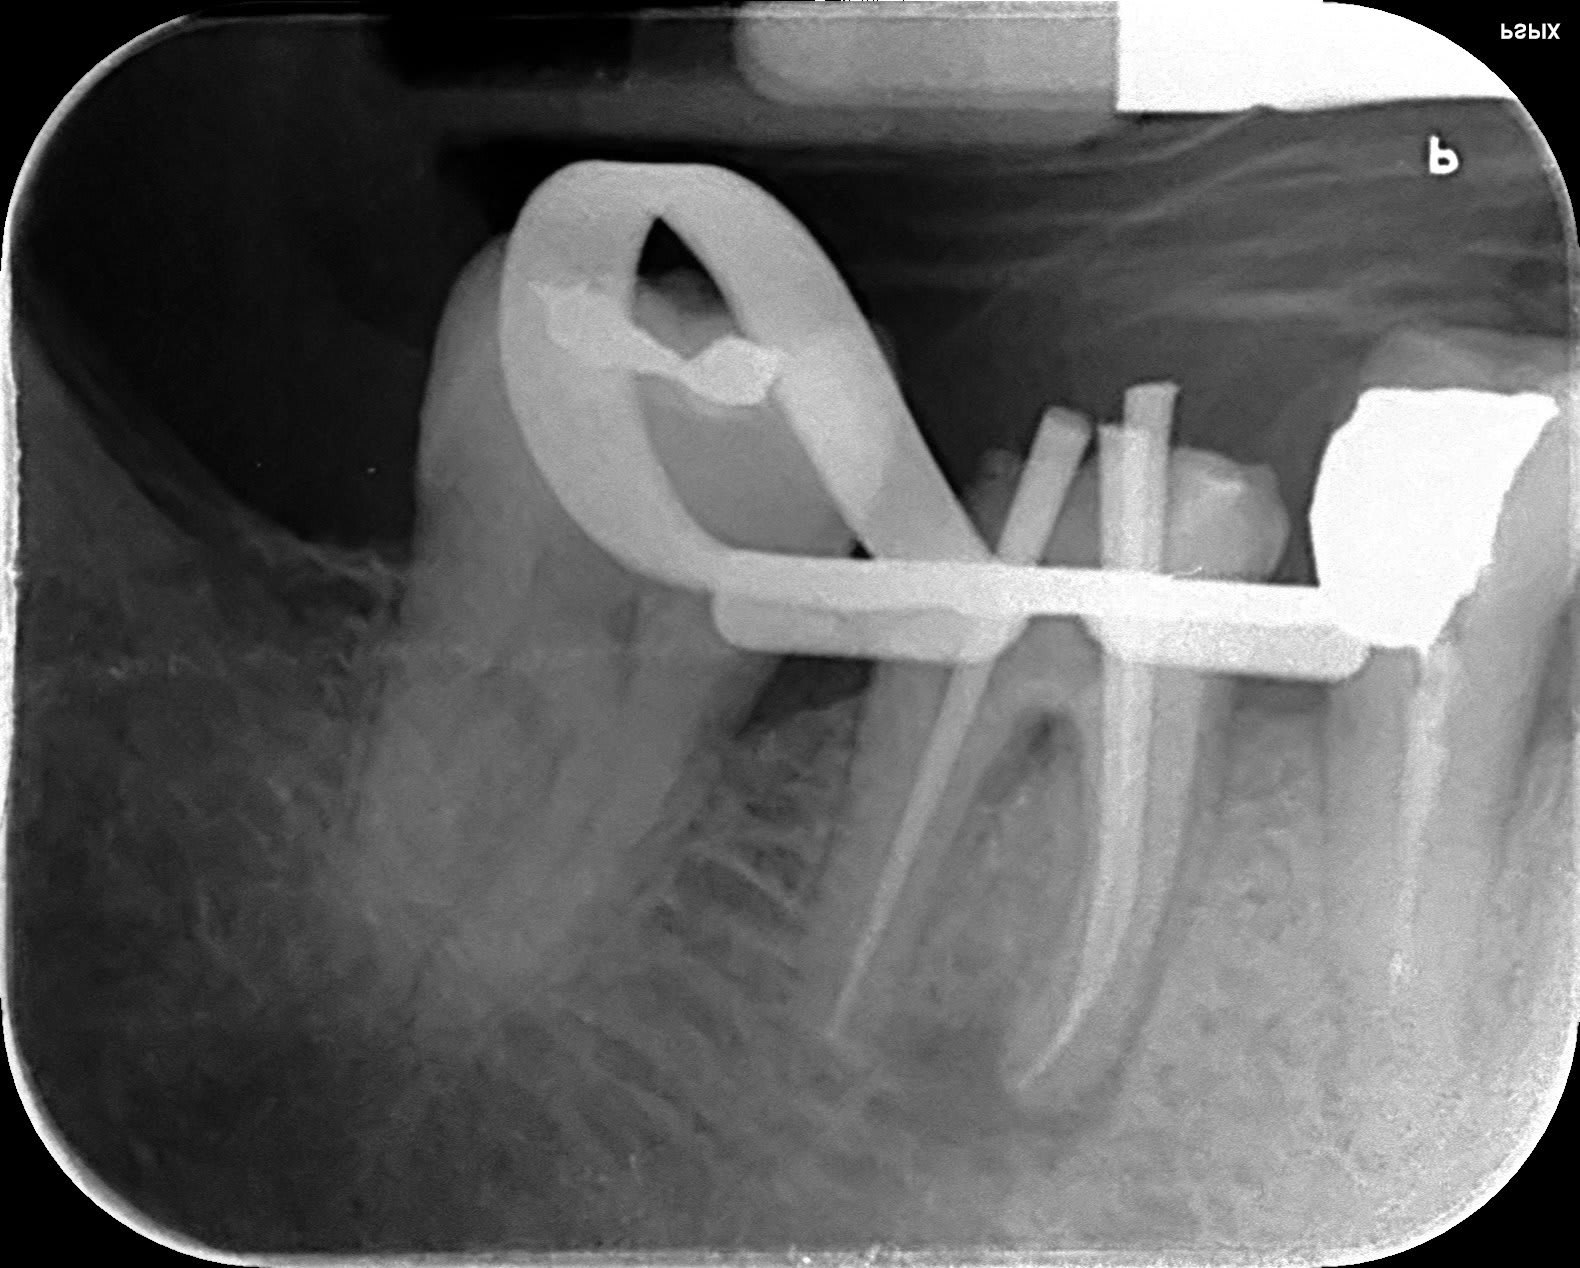

depuis le déconfinement j'ai l'impression de faire un DU d'endo:-)

47 iejkdr - Eugenol

T’en profiteras pour regarder l’occlusion mon Vulpi. Ça serait con d’avoir fait une belle endo pour rien . T’as passé le thermocompacteur ?

je sais faire que ça gutta condensor, bague bleue en 21mm. C'est plus rectiligne qu'il n'y parait et surtout c'est bien large ce qui aide, il n'y a que deux racines, M et D.

En fait, petit délire, j'avais le temps... que deux racines et patiente sympa... cone r25 racine M, finger spreader 3 cones 25 iso histoire d'avoir un bouchon et de ne pas dépasser, cone en D qui rejoint au dessus et gut cond.. est-ce rac0 compatible??? ça... ??